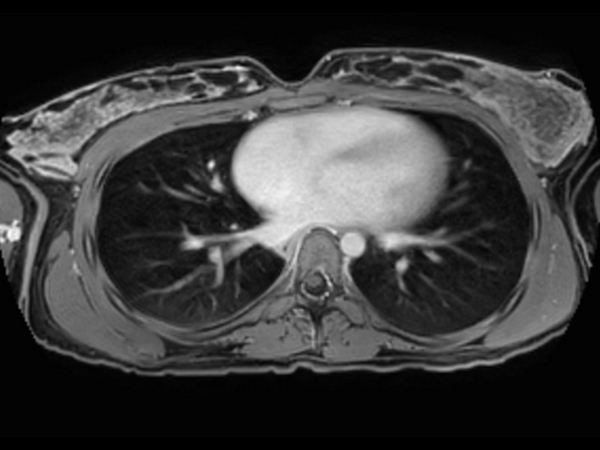

T1w mDIXON XD (Out Phase)